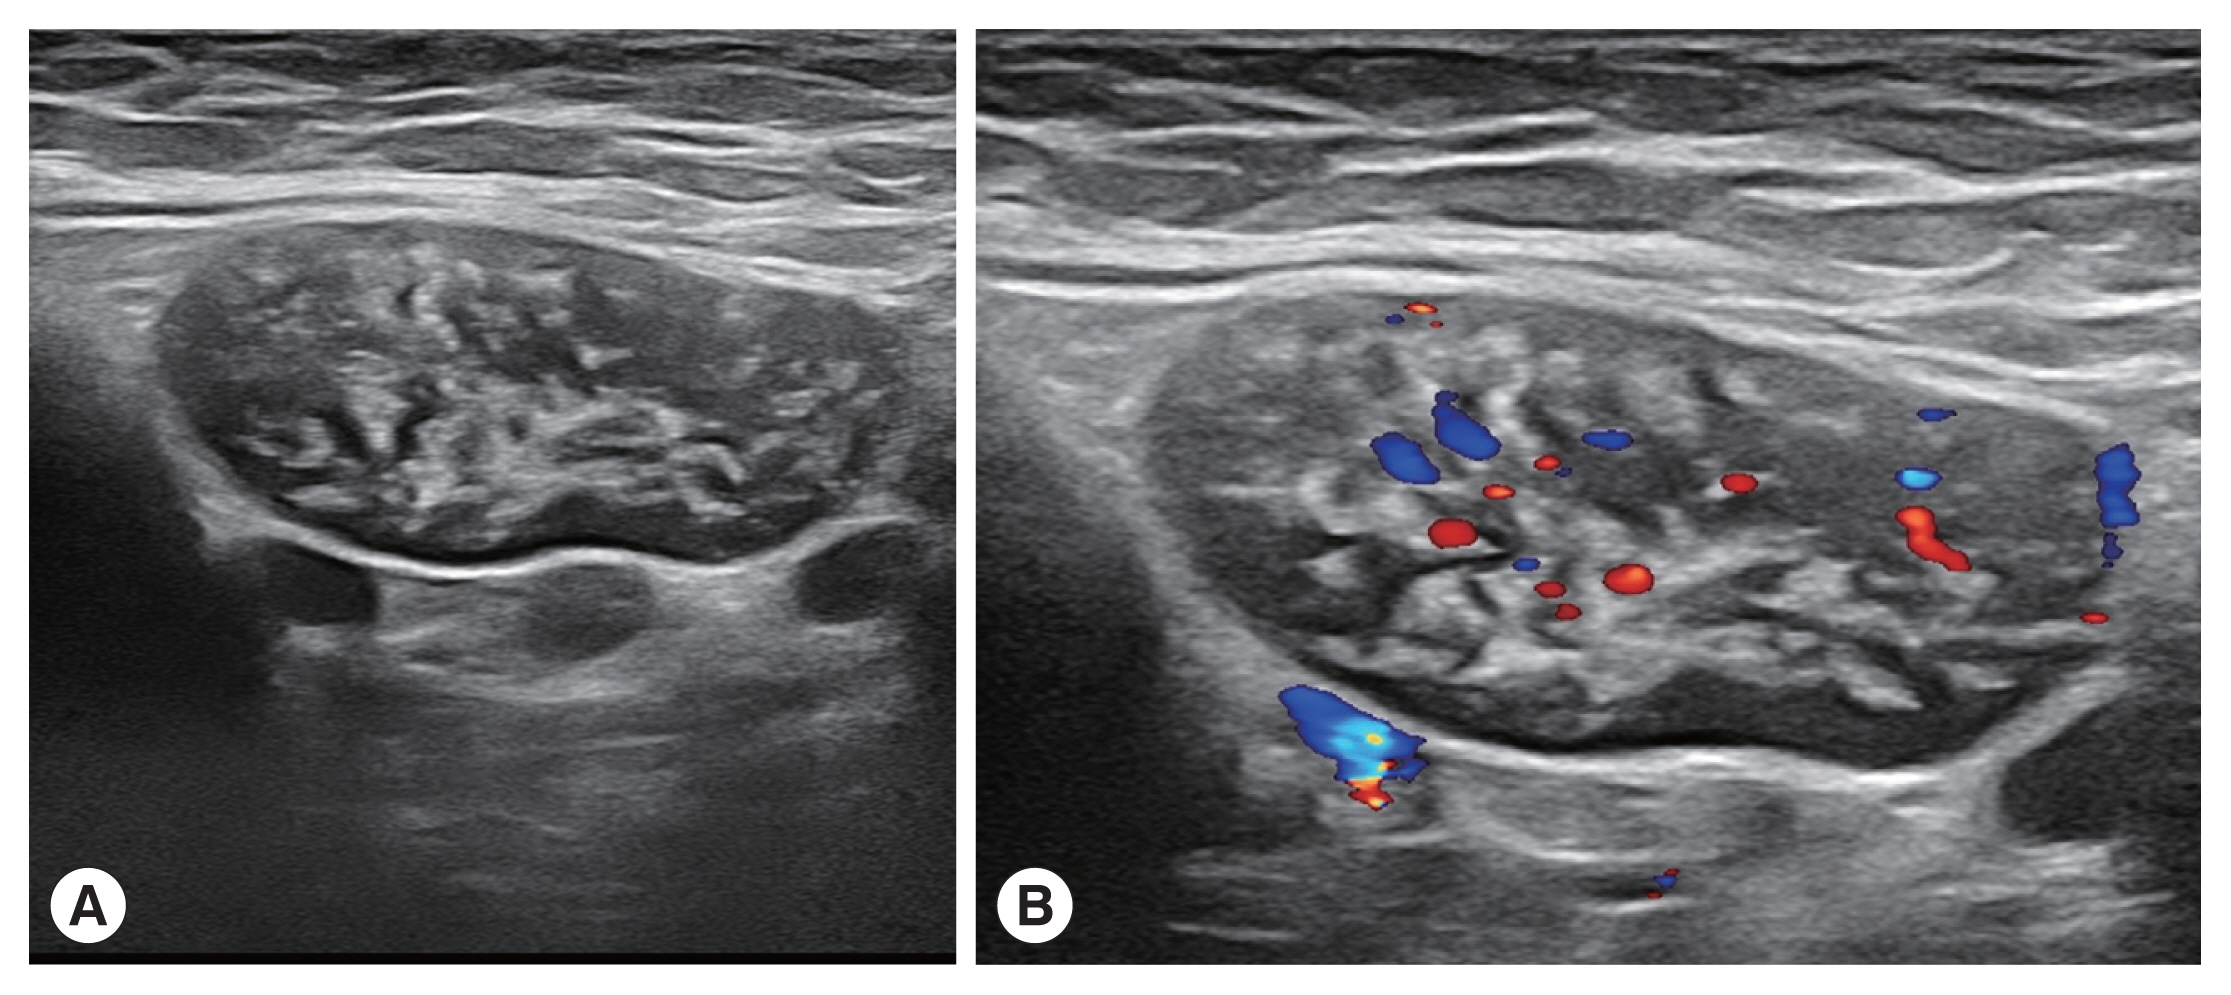

The patient was a 53-year-old woman living in Hefei City (Anhui Province). She was admitted to our department in 2022 with a small mass in the right armpit that had been persisted for over 1 month. The patient had no fever and no inflammatory manifestations in the right armpit. She had not experienced fever, chills, night sweats, or gastrointestinal, musculoskeletal, or neurologic symptoms. Her physical examination revealed a mass in the right armpit, approximately 4.0 cm×2.0 cm×1.0 cm in size. Breath sounds were normal. Complete blood counts showed a normal level of eosinophils (0.11×109/L), while red blood cell (3.66×1012/L), and hemoglobin (113 g/L). Hematocrit (0.332 L/L) levels were below the reference range. Blood coagulation functions were within the normal range. Ultrasonography of the liver, breast, thyroid gland, cervical lymph node, and inguinal lymph nodes revealed no specific lesions. Ultrasonography of the right axillary lymph nodes revealed more than 3 hypoechoic oval shaped nodules that had a clear edge. Strong-echo light spots were diffusely distributed in the hypoechoic nodules, the largest of which was 41 mm×17 mm (Fig. 1A). Color doppler ultrasonography showed that the dot-bar color doppler flow signal was relatively rich in these enlarged hypoechoic nodules (Fig. 1B). Histological examination of biopsy samples from the right axillary lymph nodes revealed granulomas containing multinucleated giant cells and elliptic calcified Schistosoma eggs (Fig. 2). In further questioning, the patient stated that 7 years prior to symptom onset, she had travelled through Yunnan province, where she had spent sometimes swimming in Lake Erhai, an endemic area for Schistosoma japonicum.